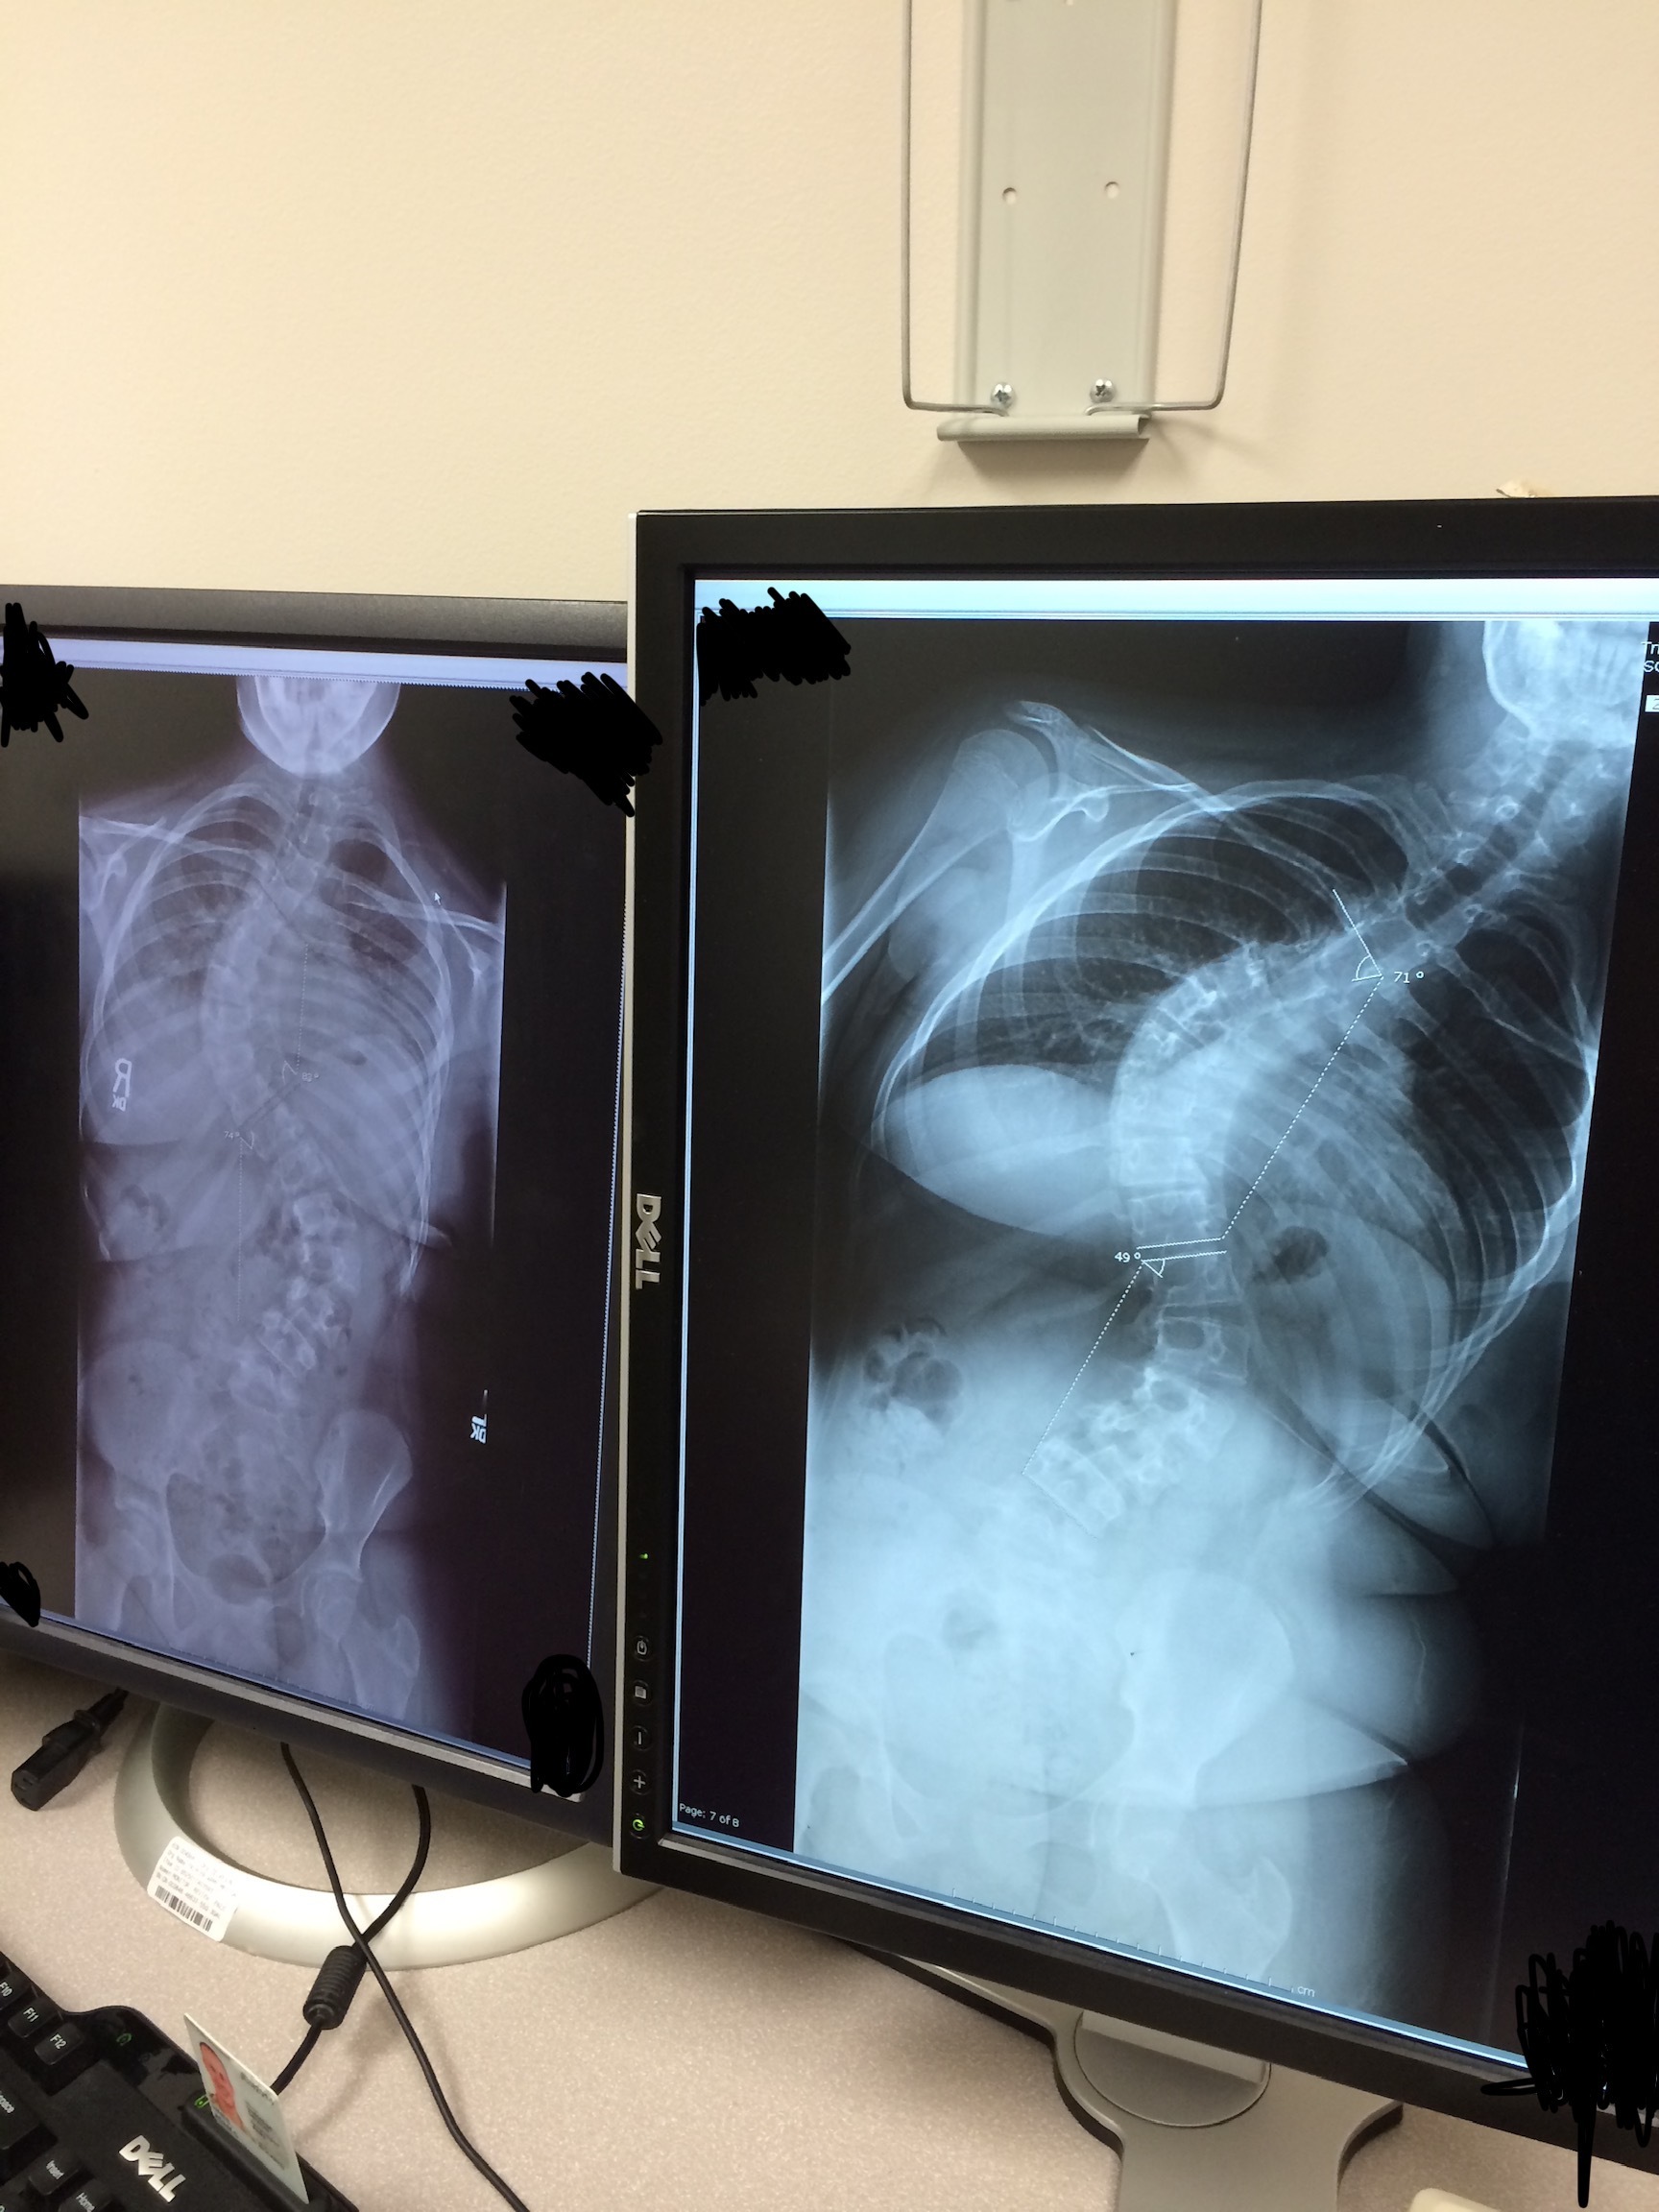

Load More Replies...so when we went for my first appointment for my scoliosis, they said the curve wouldn't progress much more so i didn't need a brace. i think it was around 30-40 degrees for both curves at that point. less than two years later the curve had progressed over ten degrees (both curves are now 50 degrees) and my spine is in the shape of an s.

I had to get a chest X-ray as a teen in order to rule out possible pneumonia (turns out I just had bronchitis). This is not the mistake. Fast forward a year later, and I was diagnosed with severe scoliosis. I had both a top and bottom curve, with surgery as the only treatment option. My mom was kind of kicking herself for never noticing, but then she remembered I had gotten that X-ray. Her and my dad went back and forth for a while about if the X-ray might have shown anything (she said it did, while he didn’t think so), and it eventually got to the point where my mom went to the hospital and requested a copy of it. Not only did it show the top curve, but the technician actually had made a point about it in the notes, and for me to be informed in order to follow up with my regular doctor immediately. The ER doctor never mentioned anything beyond "no pneumonia". So basically, I could have gotten my scoliosis diagnosed an entire YEAR earlier! Or at least been made aware of the fact that I had it.